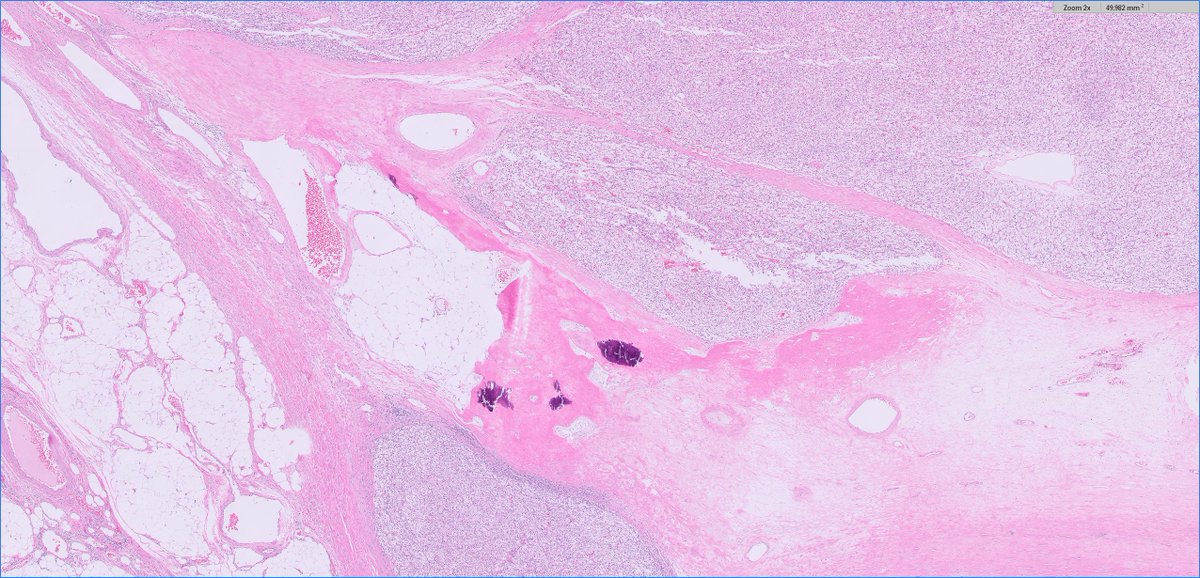

70s F, partial nephrectomy. What is your diagnosis? Gross photo in the chat. #PathTwitter

@MGBpathology @MGHPathology @PathDocBoston

6

35

92